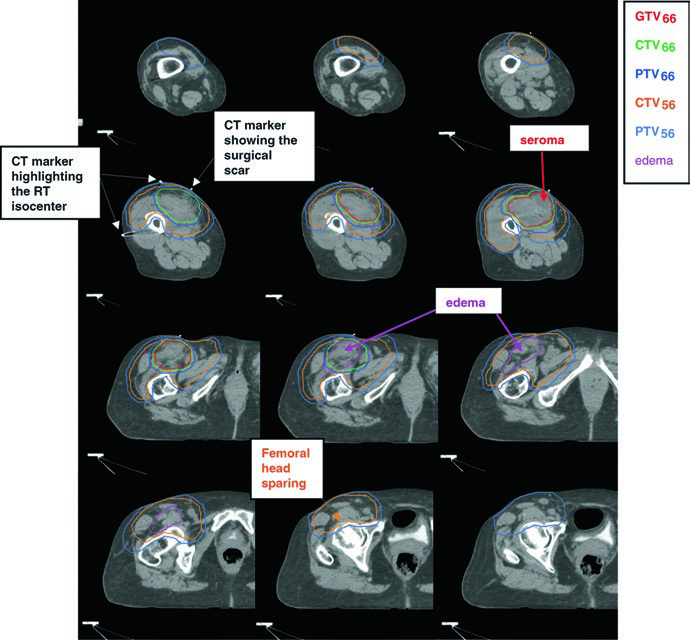

La dosis postoperatoria estándar es de 66 Gy (60 Gy puede ser aceptable en márgenes libres y bajo grado). La técnica recomendada es el boost simultáneo integrado (SIB): el CTV66 recibe dosis alta en la región de mayor riesgo, mientras que el CTV56 cubre la zona subclínica periférica a 1,69 Gy/fracción hasta 56 Gy. Para enfermedad residual macroscópica irresecable, se emplean 70 Gy en fracciones de 2 Gy según la tolerancia regional.

La comunicación con el cirujano y la revisión de los informes quirúrgico y patológico son fundamentales para decidir si el seroma, linfocele o hematoma deben incluirse en el volumen. La cicatriz quirúrgica y los drenajes generalmente quedan dentro del CTV56. Cuando los tejidos subcutáneos han sido contaminados durante la cirugía, puede aplicarse bolus sobre la cicatriz para una parte del tratamiento (por ejemplo, los primeros 50 Gy).

| GTVpostop | Identifica el sitio tumoral original. Importar imágenes prequirúrgicas al TC de planificación para garantizar cobertura adecuada de la extensión tumoral original. |

| CTV66 | GTVpostop + área de cambio quirúrgico inmediato con margen de 1–2 cm longitudinal y 1,5 cm transversal. Puede incluir tejidos manipulados, cicatrices y drenajes. |

| PTV66 | CTV66 + 0,5–1,0 cm. |

| CTV56 | GTVpostop + 4 cm longitudinal y 1,5 cm radial hasta barrera anatómica. Tejidos quirúrgicos alterados, cicatrices y drenajes con margen de 1–2 cm si no están en CTV66. Edema peritumoral contorneado por separado; RM postoperatoria reciente recomendada. |

| PTV56 | CTV56 + 0,5–1,0 cm. |

Técnica SIB: CTV66 a 2,0 Gy/fx hasta 66 Gy; CTV56 a 1,69 Gy/fx hasta 56 Gy. Alternativa: técnica secuencial de campo reducido con 50 Gy + boost de 16 Gy. Fuente: Target Volume Delineation and Field Setup, 2nd Edition (Table 32.2).

Algunos detalles merecen atención especial: puede ser necesario un bolus de 5 mm para rellenar defectos de tejidos blandos (como en el caso de injerto de piel sobre periostio con margen profundo positivo); la cabeza femoral debe preservarse como OAR limitante cuando el CTV se aproxima; y en casos de excisión no planificada, los márgenes radiales se aproximan a los márgenes postoperatorios para compensar la ausencia de GTV y la contaminación por cirugía intralesional. Para comprender cómo principios similares de respeto a barreras anatómicas se aplican a otros escenarios, como la delineación en linfoma, consulte los demás artículos dedicados de nuestra serie.